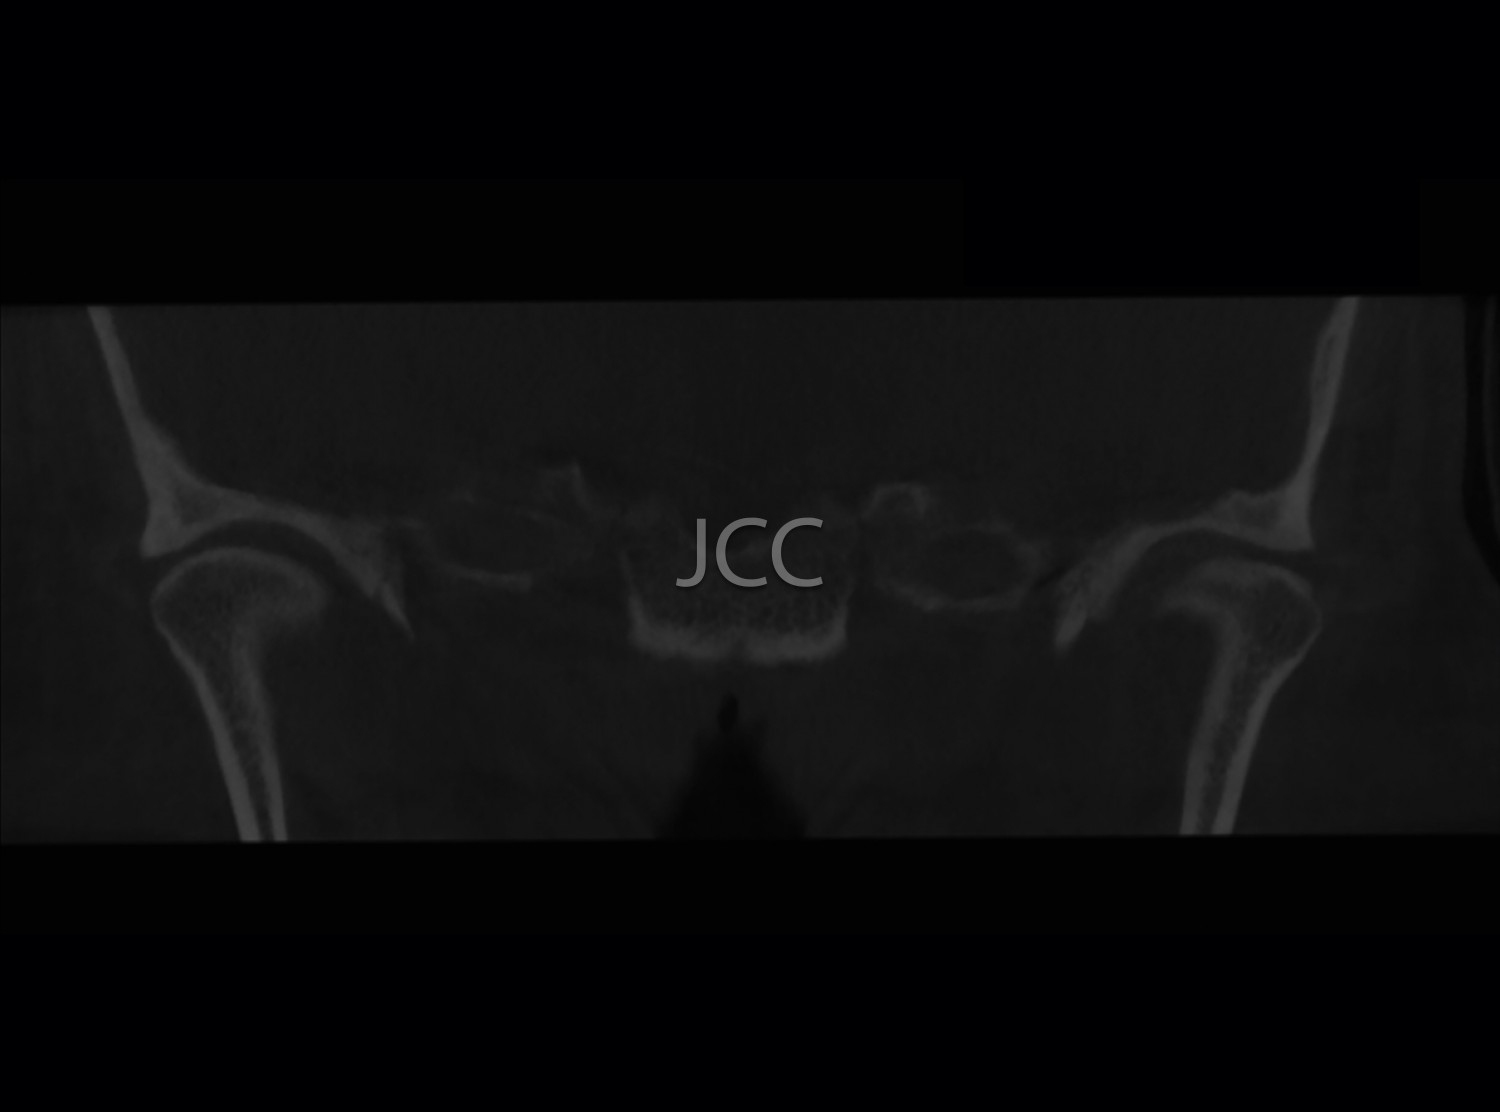

Dental Radiology - TMJ CBCT / CT

• Bone changes of the TMJ's

*Although preferably the CBCT mode is chosen, when one intends to analyse soft tissue pathologies, multi-cut CT is used.